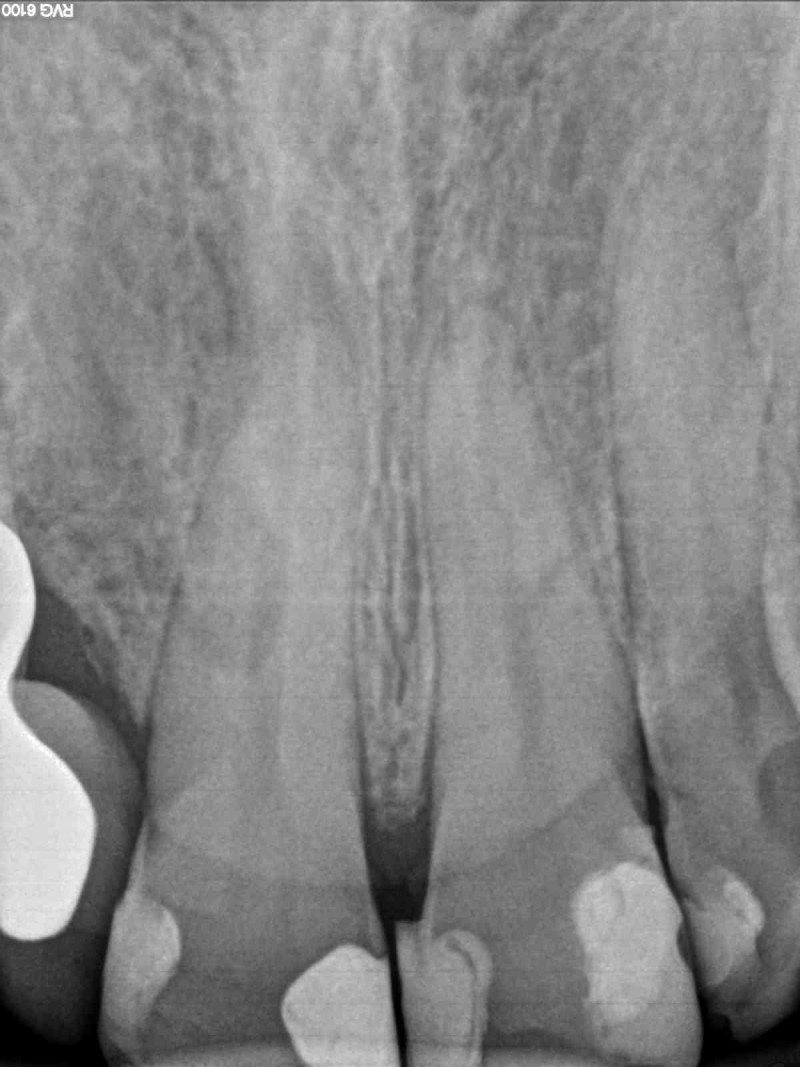

Dokumentacja RTG

- OPG przed zabiegiem wykonane przez lekarza prowadzącego

- RVG

- CBCT przed i po zabiegu